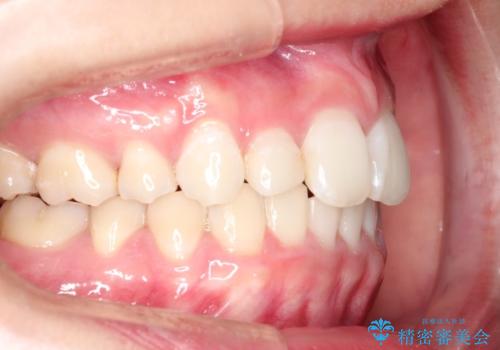

ハーフリンガル矯正 抜歯をして前歯を下げる

上顎の抜歯により上の前歯の位置を大幅に後ろに下げることができます。

奥歯の位置関係など、様々な要素を加味し、適応を判断する必要があります。